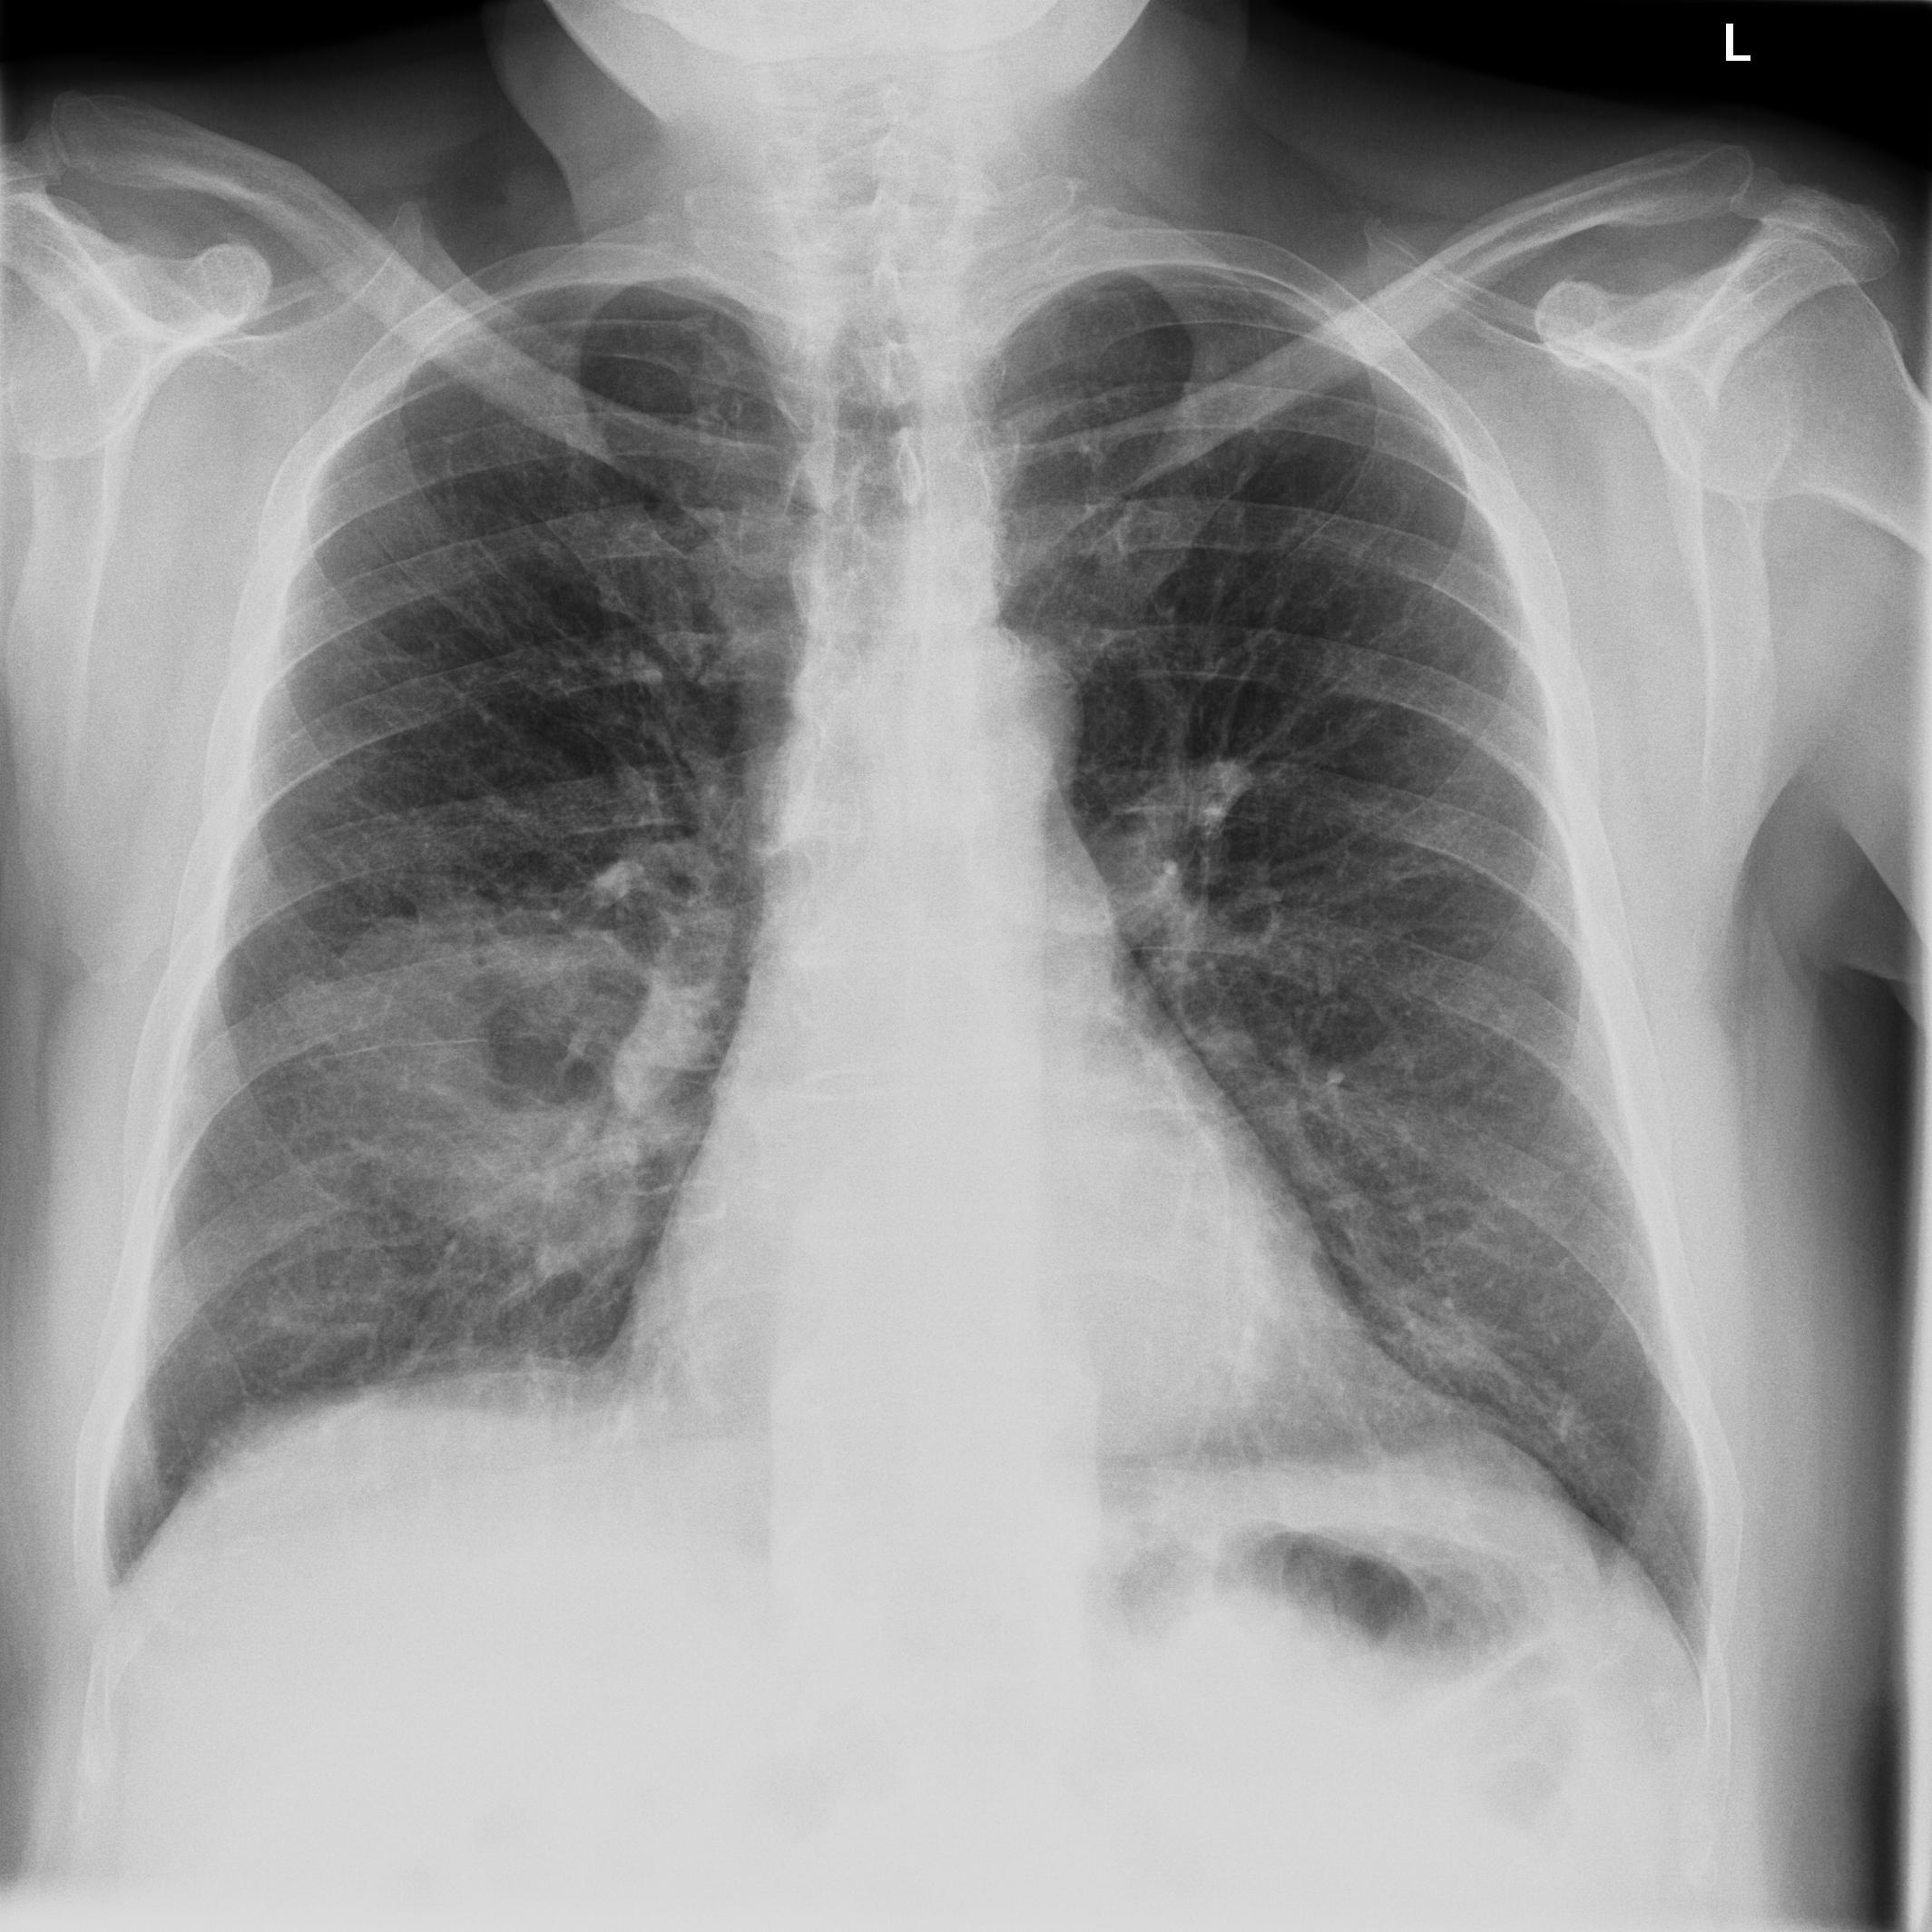

3.3 X-Ray

X-ray imaging is a fundamental form of radiography. Reducing radiation dose while maintaining image quality is a key principle in radiology known as ALARA (As Low As Reasonably Achievable) (citep \@BBN(Schiska, 2021)). New technologies and imaging techniques, such as post-processing by artificial intelligence (AI) (citep \@BBN(Harvey and Topol, 2020)), may allow diagnostic objectives to be achieved with lower radiation doses. Furthermore, advancements in X-ray have also the potential to influence and enhance Computed Tomography (CT) (citep \@BBN(Feghali et al., 2021)). Whereas CT requires complex imaging reconstruction algorithms, X-ray is more straightforward, employing post-processing for high-quality and detailed imaging. This is crucial for clinical assessment of anatomical structures and potential pathologies, being often used to guide treatment decisions and to plan interventions, such as surgery or radiotherapy.

3.3.1 Post-processing problem

The raw data captured during digital radiography reflects the pattern of X-ray attenuation by different tissues. The digital signal is then processed to create a greyscale image, where each shade corresponds to the radiodensity of the tissues, ranging from black for air through varying shades of grey for soft tissue and white for bone. Post-processing software refines the raw image to enhance clarity and diagnostic utility (citep \@BBN(Seeram and Seeram, 2008)). This may involve adjusting parameters such as brightness and contrast, applying filters for noise reduction, or using algorithms for edge enhancement (citep \@BBN(Krupinski et al., 2007)). The aim is to produce an image that provides the best possible diagnostic information while adhering to the ALARA principle.

Different quality properties may be desired depending on the purpose of the X-ray. For example, when visualizing the lung tissue, adjustments are made to the brightness and contrast to best highlight the anatomy and common abnormalities whilst minimizing noise. However, noise is less important when aiming to confirm the position of a line, tube, or foreign object. In this case, an image with edge enhancement and adjusted brightness levels may be desirable to amplify the distinction between the dense material of the object and the surrounding soft tissue.

Quality control for the provided default post-processing is usually made by the manufacturers themselves, therefore not accessible to the end user, and may be divergent to the IQ needed for clinical images (citep \@BBN(Tsalafoutas et al., 2024)). After the machine has been placed in the hospital environment, personalized post-processing settings are often determined by subjective visual inspection. Objective evaluation would help to find an optimal post-processing type for visualization, allowing faster and consistent evaluation. Beyond this setting, objective IQA is important for the development and testing of machine learning algorithms on chest X-ray images including super-resolution, denoising or inpainting methods, where PSNR and SSIM are currently the standard choice for quality assessment, see e.g. (citep \@BBN(Tran et al., 2021; Mandić et al., 2018; Wang et al., 2021; Thanh et al., 2020; Jiang et al., 2021)).

3.3.2 Data

Posteroanterior chest radiographs were acquired on two imaging systems (both Discovery XR656 HD models, GE Healthcare, USA) at Cambridge University Hospitals NHS Trust. Each scanner was being set up in the hospital with different post-processing parameters (chosen by the operating radiologists), which are used here as reference images, see Figure 7 and 8(a). Additional images, serving as real-life examples of lower quality, were produced for each radiographic exposure using multiple different post-processing settings. The post-processing was applied in the hospital directly on the scanner itself by adjusting parameters in the provided framework.

Refer to caption

(a) Reference

(b) (21.1, 0.90, 0.11)

(c) (19.5, 0.88, 0.16)

Figure 7: Chest X-Ray scans with different kinds of post-processing; (a) serves as reference and (b) is wrongly judged as better visualization by PSNR/SSIM/LPIPS.

(b) (22.8, 0.97, 0.08)

(c) (21.2, 0.96, 0.07)

Figure 8: Chest X-Ray scans with different kinds of post-processing; (a) serves as reference, (b) is wrongly judged as better visualization by PSNR and SSIM, LPIPS gives a slightly worse evaluation for (b).

In Figure 7, contrast deviation and edge enhancement were reduced in (b), but increased in (c), the noise reduction algorithm was removed in both. The brightness was increased in both images but more so in (c) and low-contrast enhancement was removed in (b). The result is that (b) has relatively low contrast in the lungs compared to the reference (a) and radiograph (c). In Figure 8, edge enhancement has been dramatically increased in (b), whilst the contrast deviation and tissue contrast have been reduced. In (c), the brightness, tissue contrast and edge enhancement have been slightly increased. Consequently, (b) provides low contrast in the lungs with excessively prominent lung markings and vasculature which make it harder to detect abnormalities such as a pneumonia.

FR-IQA mismatches

In Figure 7 and 8 we apply the standard FR-IQA metrics to the images with diverging quality. Although it is visually obvious that image (b) has lower visual quality, it is judged wrongly as the better image by all measures in the first example Figure 7, and the results in (b) and (c) of the second example Figure 8 are quite close, where PSNR and SSIM are also providing the wrong order. This indicates that the tested standard FR metrics are not suitable to evaluate the quality of data sets with X-Ray images that have large variations regarding contrast, luminance and sharpness.